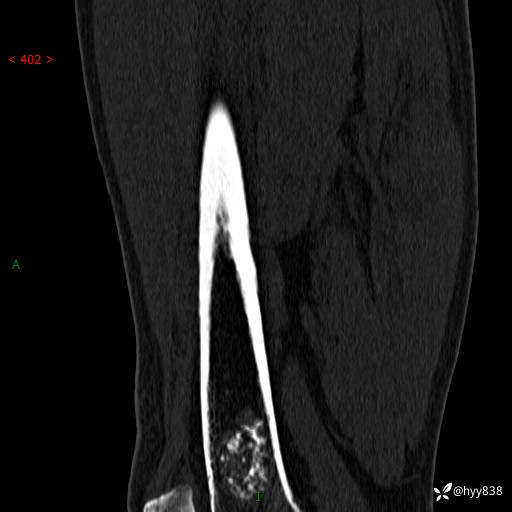

CT

img